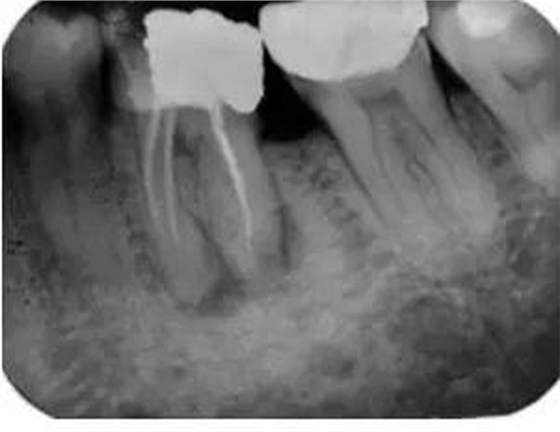

如果根管內(nèi)有樁、折斷的器械或根充物,那么該患牙的治療難度就會增加(圖3)。樁能否從根管內(nèi)取出取決于樁的大小和形態(tài)。如果根管內(nèi)的折斷的器械位于根尖三分之一和彎曲根的根方,將折斷器械取出來的難度要比在冠方的更困難。